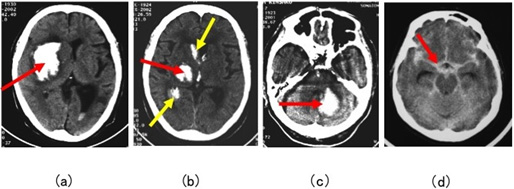

図15:頭蓋内出血の4症例の頭部CT

- 右被殻出血(赤→)。強い左片麻痺をきたす。

- 右視床出血(赤→)。脳室内にも広がっている(黄→)。

- 左小脳出血(赤→)。めまい、嘔吐と頭痛で発症。

- くも膜下出血(赤→)。脳内の出血ではなく、脳表の髄液内に出血が広がる。